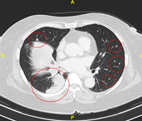

因胸悶、喘、痛就醫。電腦斷層顯示右下肺巨大肺腫瘤與雙側肺轉移。